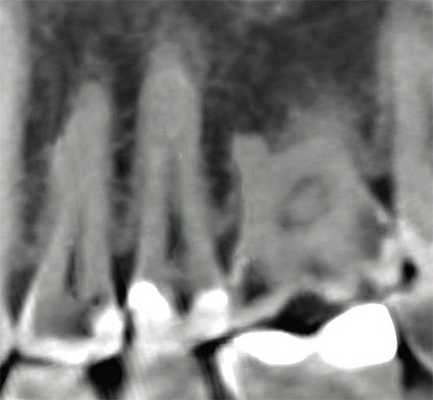

(Справа) На периапикальной рентгенограмме определяется средний кариес с поражением цемента на дистальной поверхности второго моляра нижней челюсти слева. Наличие тонкой полоски дентина не препятствует микробной инвазии пульпы; определяются признаки периапикального рарефицирующего остеита. Кариозное поражение не распространяется ниже уровня кости. (Слева) На сагиттальной КЛКТ определяется глубокий кариес с поражением цемента на дистальной поверхности первого моляра верхней челюсти. Обратите внимание на разрежение костной ткани возле периодонта со троны дистальной поверхности этого зуба.

(Справа) На аксиальной КЛКТ у этого же пациента определяется кариес цемента, подходящий к области фурка-ции пульпы. Признаки кариеса на КЛКТ обнаружены случайно; КЛКТ не должна использоваться для диагностики кариеса, предпочтение необходимо отдавать интраоральной рентгенографии - более точному методу диагностики, связанному с меньшей лучевой нагрузкой. (Слева) На профильном срезе (КЛКТ) премоляра нижней челюсти, восстановленного реставрационным материалом (V класс), определяется рецидив кариеса корня на лицевой поверхности зуба. Со троны лицевой поверхности определяется углубление в костной ткани возле периодонта.